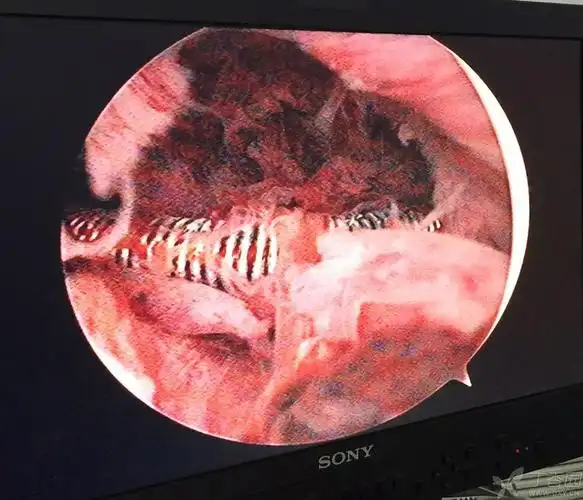

绝经后取环一例

节育环"长进肉里了",垫江县人民医院妇科有办法

绝经近10年取环

节育环在宫腔形态